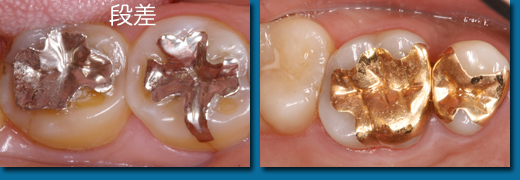

虫歯を削ったところに詰める材料にはいろいろあります。小さい虫歯はコンポジットレジンという硬いプラスチックで埋めますが歯と同じ色で治療も一回で済みます。大きなものでは強度が必要となり金属かセラミックを使用します。保険で使用する銀色の金銀パラジウム合金は硬すぎて使っていくうちに周りの歯との間に段差が出てきます。ゴールド系の金属は柔らかいので段差がでにくいのが特徴です。セラミック系のものはきれいですが割れやすいのが難点です。小さな虫歯のうちに治しておくのが得策です。

奥歯にはものを噛む大切な役割があります。人間の噛む力には個人差がありますが自分の体重くらいの力が一本の歯にかかるので壊れないことが大切です。また自分の歯は年齢とともにすり減っていくのであまり硬すぎる歯が一本だけあってもバランスが取れません。壊れにくさでは金属が丈夫であり見た目の良いセラミック系は割れることがあります。硬さではセラミック系、保険の銀、ゴールド系の順番で硬くゴールド系の冠が最も自分の歯に近い硬さです。